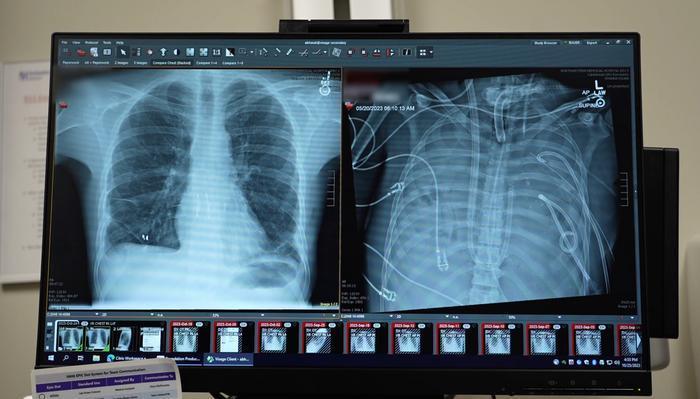

患者是一名33岁男性,因流感继发细菌性肺炎,导致急性呼吸窘迫综合征(ARDS)。他的双肺在感染与炎症冲击下迅速恶化,并逐步引发心、肾功能衰竭。常规治疗已无法控制病情,肺移植成为唯一生存希望。然而,由于感染过重、全身状态极差,患者当时无法立即接受移植手术。

为破解“无肺期”的生命维持难题,医疗团队设计了一套人工肺系统,在患者完全无肺的状态下暂代肺功能,为血液供氧、清除二氧化碳、帮助维持心脏及全身的血流稳定。在切除严重感染的双肺后,患者的血压逐渐平稳,器官功能开始恢复,感染也得到控制。48小时后,等到了匹配的供肺,团队成功为他完成了双肺移植。